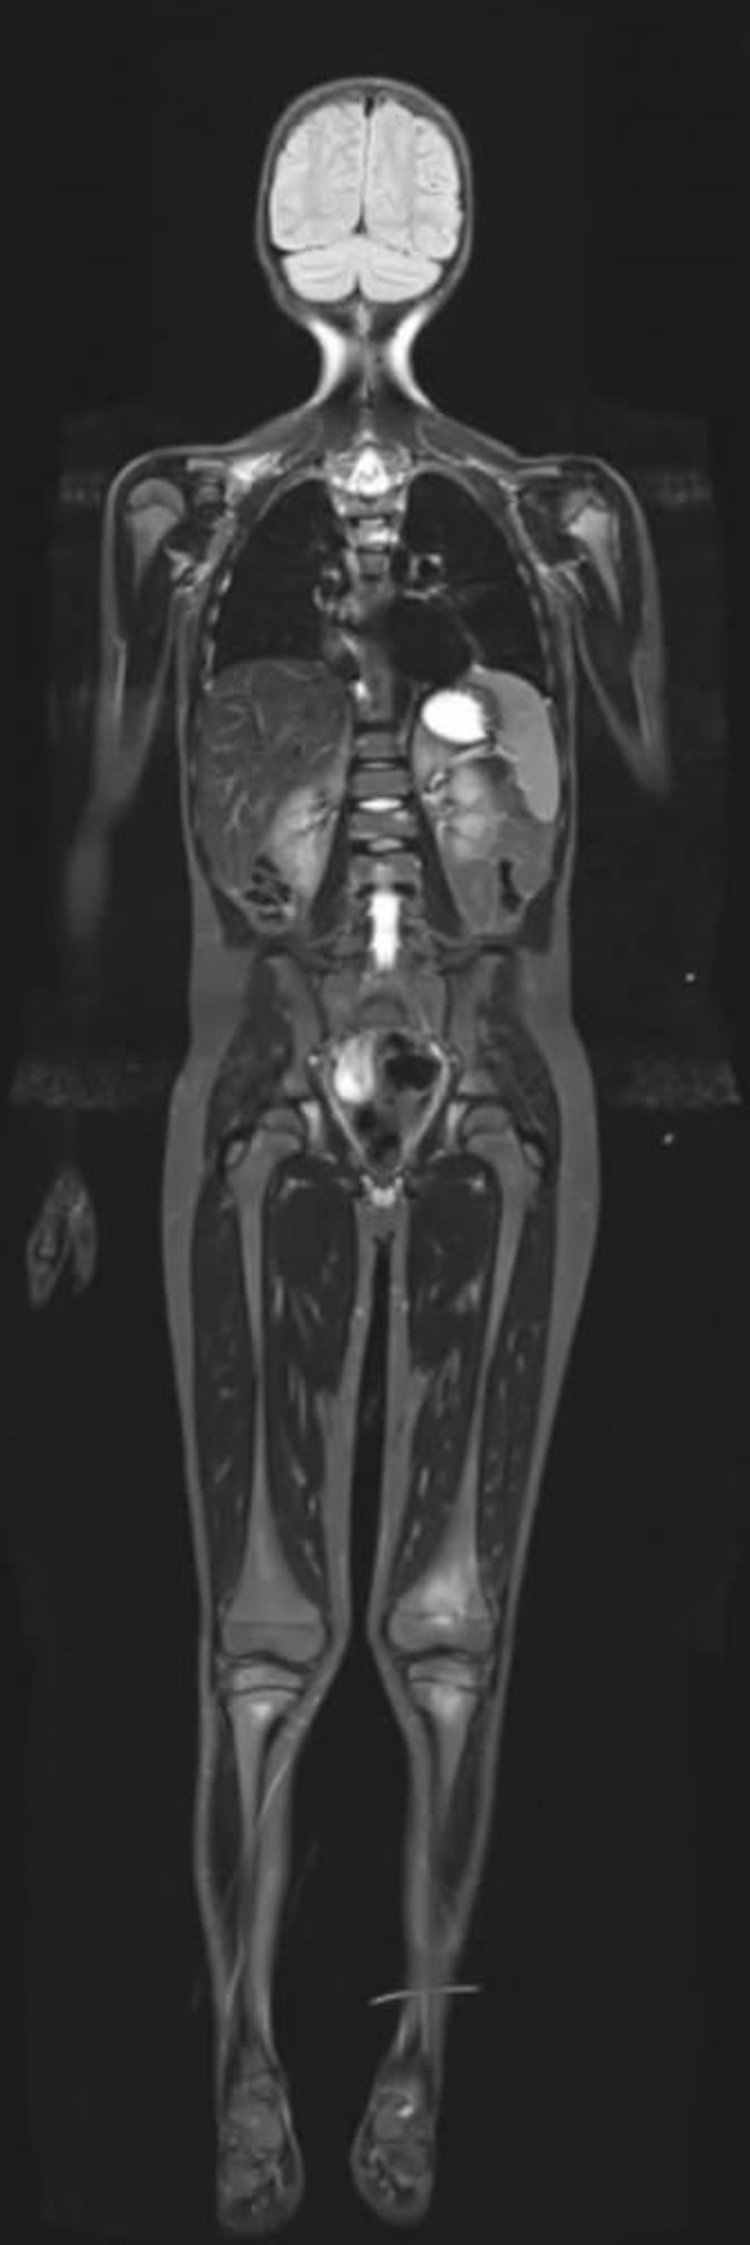

全身のshort, tight inversion recovery MRI

Image courtesy of Hakan Ilaslan, MD.